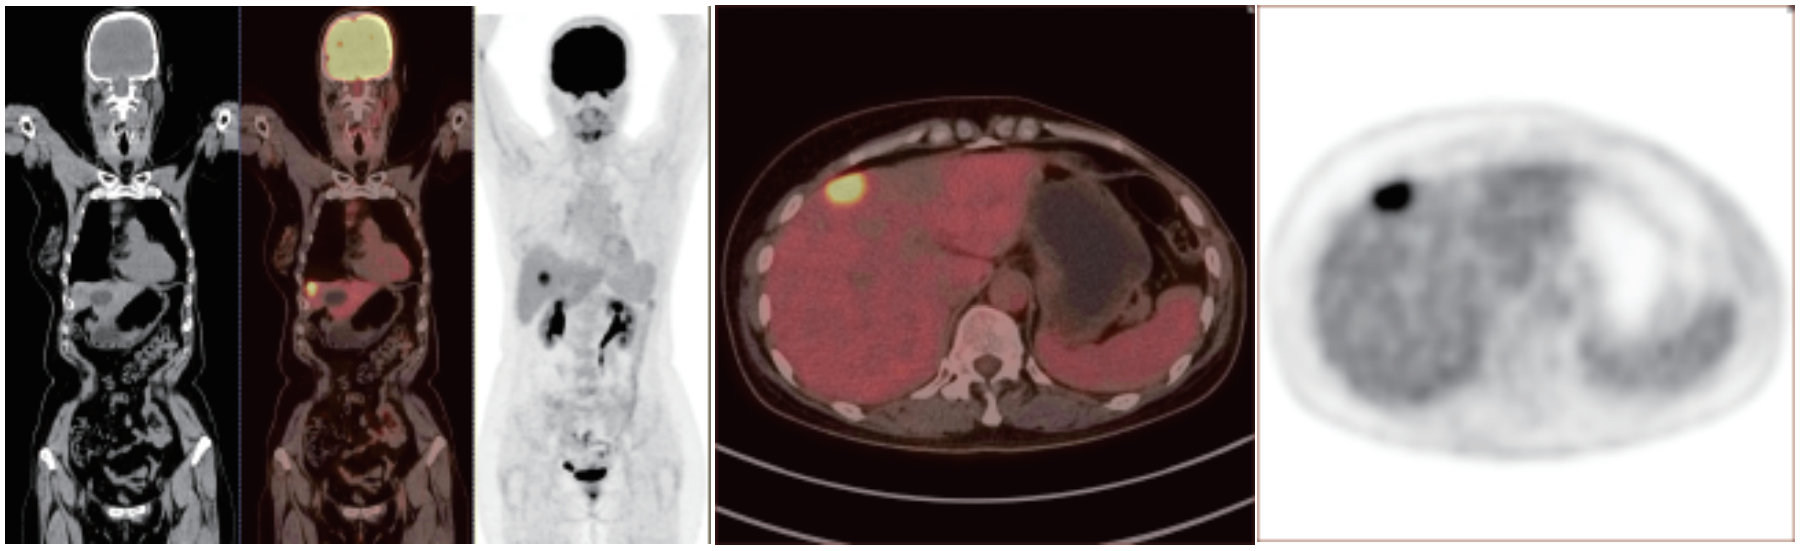

PET/CT在全身腫瘤的早期篩查、早期診斷、 良惡性鑒別、惡性腫瘤的分期、分級、尋找腫瘤原發(fā)病灶、評估療效及監(jiān)測腫瘤復(fù)發(fā)等方面具有重要價值。

相關(guān)病例成像圖